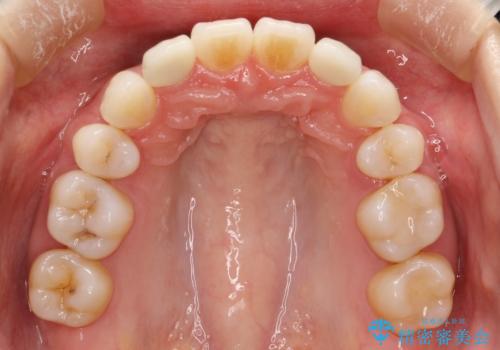

- 出っ歯と全体をきれいにしたいとのことで来院されました。

上顎の歯が全体的に前方に位置しているのと、前から2番目の歯が通常よりも小さい矮小歯という状態でした。

出っ歯をなおすために上顎の前から4番目の歯を抜歯して、引っ込めるのと、前から2番目の歯に通常の大きさのオールセラミックを装着して整った歯並びにすることにしました。

歯の大きさが通常と異なる場合は矯正治療で歯並びだけきれいにしても、整わないことがあります。

その場合はセラミックのかぶせ物を装着して歯の形を正常にすることで、さらに整った歯並びにすることができます。